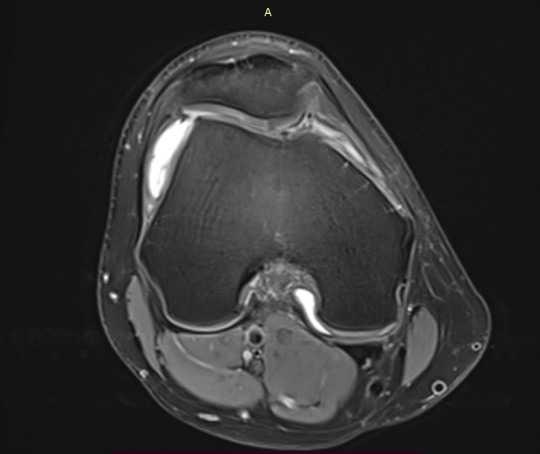

MRI